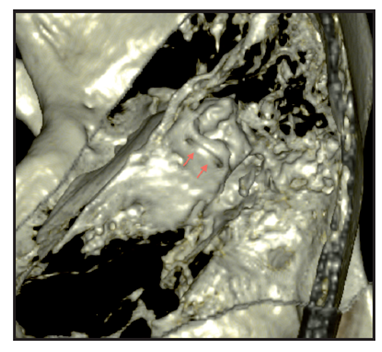

Figure 4b Rendering reconstruction volume highlighting the defect adjacent to the upper wall of CSCS, shown by arrows 4c rojas. Figure bone surface. MPR oblique parallel to the plane of the CSCS which highlights the ósea.VCL wall dehiscence. With the clinical suspicion of DCSS syndrome in left ear temporal bone CT is performed, with cuts of 0.5 mm, which confirms the clinical diagnosis.